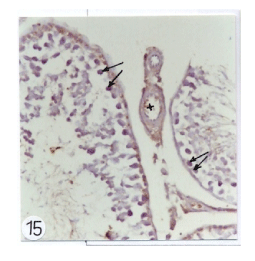

| Figure 15: Photomicrographs of testes sections of rats treated with insecticide mixture of (1/60 of LD50 of chlorpyrifose and 1/200 LD50 of fenitithione) showed signifi cant increase in the brown positive cells within the primary stages of germ cells (arrows). |